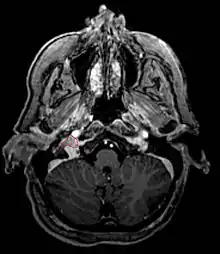

Paragangliome du glomus jugulaire